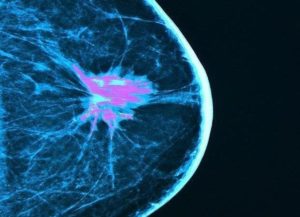

Activating Innate Immunity in Triple-Negative Breast Cancer and Other Tumors

Dr. O’Day’s was interviewed about his data from the open-label phase II IMPRIME 1 clinical trial presented as part of the 2020 American Association for Cancer Research (AACR) Virtual Annual Meeting (Abstract CT073). In this interview Dr. O’Day discusses the rationale for using Imprime PGG (a novel innate immune activator) to trigger immunity and possibly enhance response to pembrolizumab in patients with metastatic triple-negative breast cancer. He also explores the treatment’s potential in other tumor types.